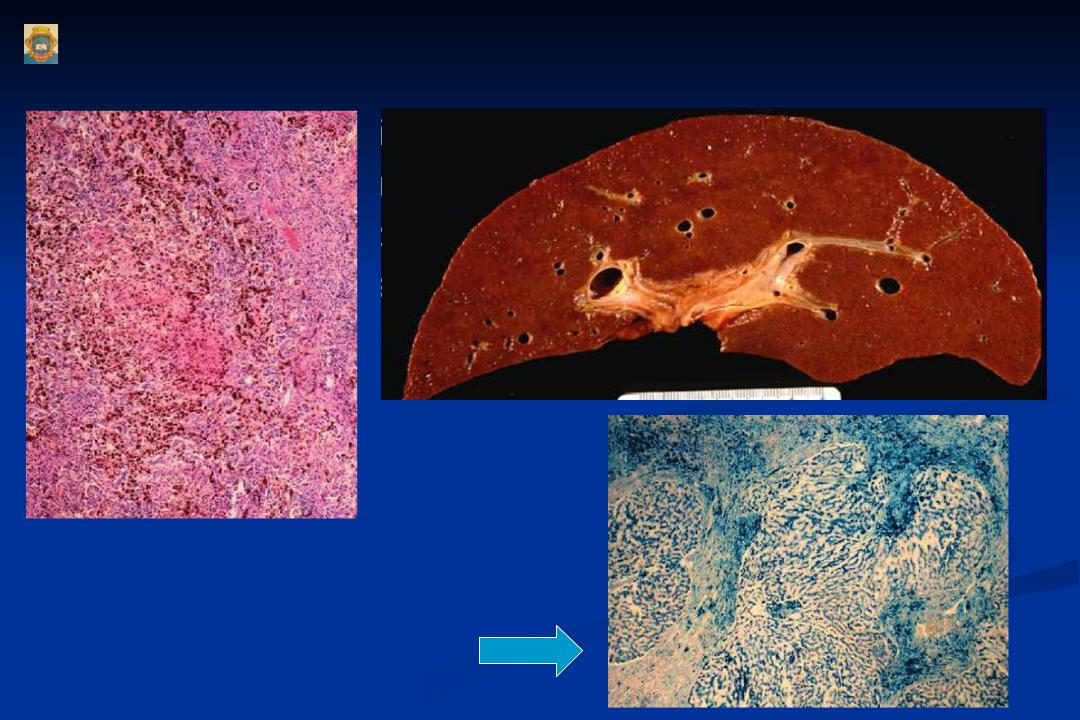

В зависимости от распространенности патологического процесса различают локальный (местный) и генерализованный (общий) гемосидероз. Локальный гемосидероз служит результатом экстраваскулярного гемолиза, т. е. внесосудистого разрушения эритроцитов. Местный гемосидероз может развиваться как в очагах ограниченных кровоизлияний (гематомах), так и в пределах целого органа (легкого, кожи). Генерализованный гемосидероз является следствием интраваскулярного гемолиза — внутрисосудистого разрушения эритроцитов при различных общих заболеваниях. В этом случае гемосидерин депонируется в клетках печени, селезенки и костного мозга, придавая органам бурую («ржавую») окраску.